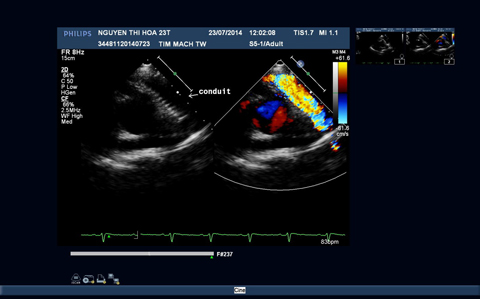

Hình 3: Hình ảnh siêu âm tim trước và sau phẫu thuật

3B: Hình ảnh đoạn mạch nhân tạo thông tốt giữa thất phải và hội lưu động mạch phổi.